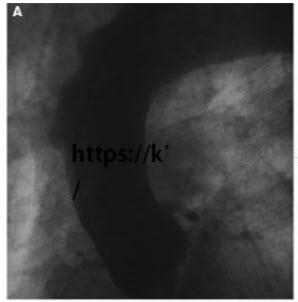

Despite severe atheroma in the aorta, the physician taking care of the patient is not convinced that he does not have an acute coronary syndrome and performs a cardiac catheterization. It shows that the grafts are patent and there is no culprit lesion in the native vessels. He then decides to perform aortography and a focal outpouching is seen in the aortic wall in the distal ascending aorta (Fig. below).

Contrast dye collects slowly in this region. The patient’s chest pain is intensifying. A TEE is also performed (Fig. below).